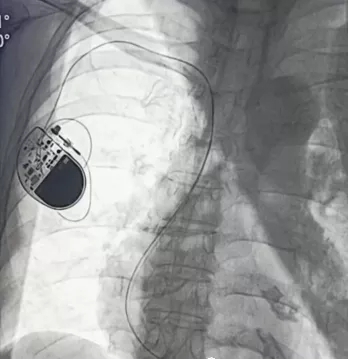

3、心脏装了起搏器后,还能做内瘘吗?

起搏器一般安装在右侧锁骨下通过锁骨下静脉放置,所以如果是在左侧上肢做瘘影响不大;如果是在同侧上肢做瘘,起搏器的置入远期可能会造成中心静脉狭窄,导致内瘘流出道梗阻,进而出现瘘体肢体肿胀等并发症。但是,临床上,也有少数病人虽然同侧有起搏器,但同侧做了内瘘后,短期内也未出现并发症,但这种患者,需要我们长期观察其有无并发症。

心脏起搏器术后胸片▲